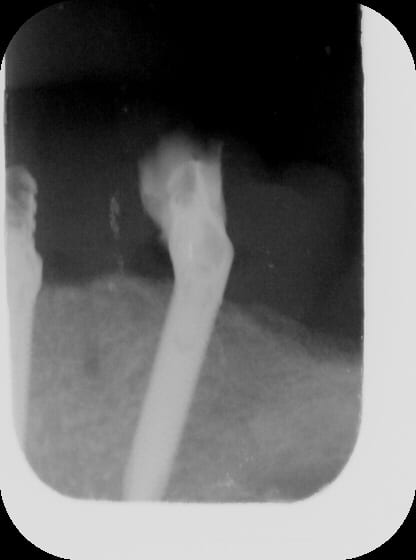

je vous montre le bas ;) oups!

(rrrhhh....les radio, dans ces secteurs là aplatissent tout, on dirait des implants presque parallèles... rrhhhh...)

Gin1 vfjd6v - Eugenol

Gin2 lzgl9h - Eugenol

Gin3 zmirus - Eugenol